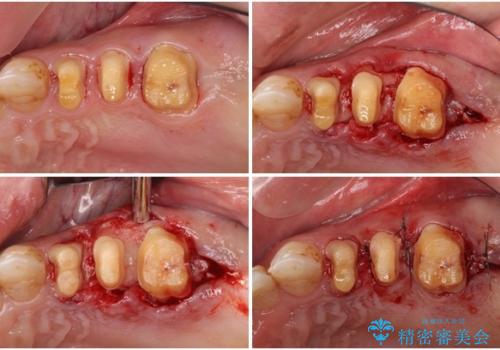

矯正治療を希望して来院されましたが、歯周病を併発していたため、矯正治療開始前の処置が非常に多くなりました。特に歯槽骨の再生治療を行ったため、外科処置後の静置期間が長くなり、4年弱の治療期間となりました。